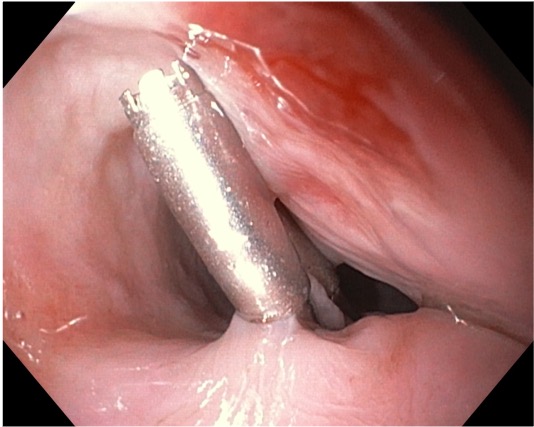

Aortoesophageal fistula: A rare cause of upper gastrointestinal bleeding

A 86-year-old male with hypertension, diabetes and ischemic heart disease, was admitted in the emergency department due to melena with hemodynamic instability. On upper endoscopy no lesions were found. He was admitted in the ICU and next-day reassessment esophagogastroduodenoscopy was normal. On the eighth day of hospitalization, the patient had new-onset hematemesis with hemodynamic instability. Esophagogastroduodenoscopy revealed an esophageal 10mm non-ulcerated mucosal depression with a visible vessel at 20cm from the incisors, closed with 3 hemoclips. Thoracic CT angiography showed a brachiocephalic trunk aneurysm with aortoesophageal fistulization. He was not a candidate for vascular treatment. No rebleeding at 2-month follow-up.